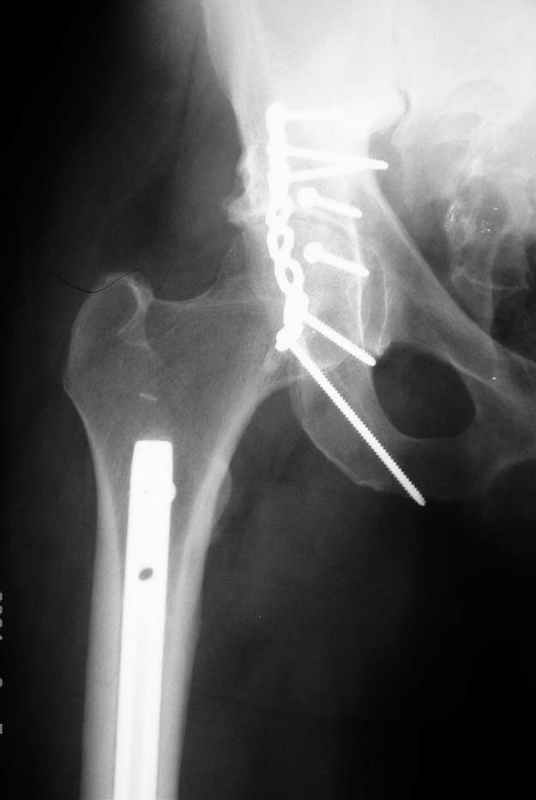

Не дождавшись советов, в понедельник прооперировал больного, заняло времени..., но все сделал в один этап: сначала фиксировал ипсилатеральный перелом бедра и шейки реконструктивным гвоздем Smith&Nephews, потом из расширенного илеофеморального доступа фиксировал перелом крыла подвздошной кости тягловым винтом, нейтрализующей пластиной заднюю колонну, и тягловыми винтами 3,5 мм переднюю колонну.

К сожалению, набора для ретроградного или антеградного реконструктивного штифтования в операционной нет, поэтому доставка заняла н-ное время. Вопрос, который возник у меня- по поводу оптимальной тактики хирургии: вся фиксация в один этап из расширенного доступа или последовательно сначала бедро и позже реконструкция впадины, комбинированный доступ к впадине отдельно к передней и задней колоннам или из расширенного илеофеморального одного доступа. Все-таки решил остановиться на одноэтапном подходе и спустя 5 дней (как раз и наборы привезли) из расширенного илеофеморального доступа сначала фиксировал реконструктивным штифтом Smith&Nephews бедро и

шейку (благо перелом шейки 2 типа -относительно стабильный) затем фрагмент крыла подвздошной кости Lag screw, далее пластина на заднюю колонну и винты в переднюю колонну.(с размерами и направлением винтов ошибка вышла:-((, но интраоперационно у меня была полная уверенность , что винты *ушли* в лонную кость).

Еще раз спасибо за комментарии и готовность помочь с имплантами. Постоп картинки в приложении,